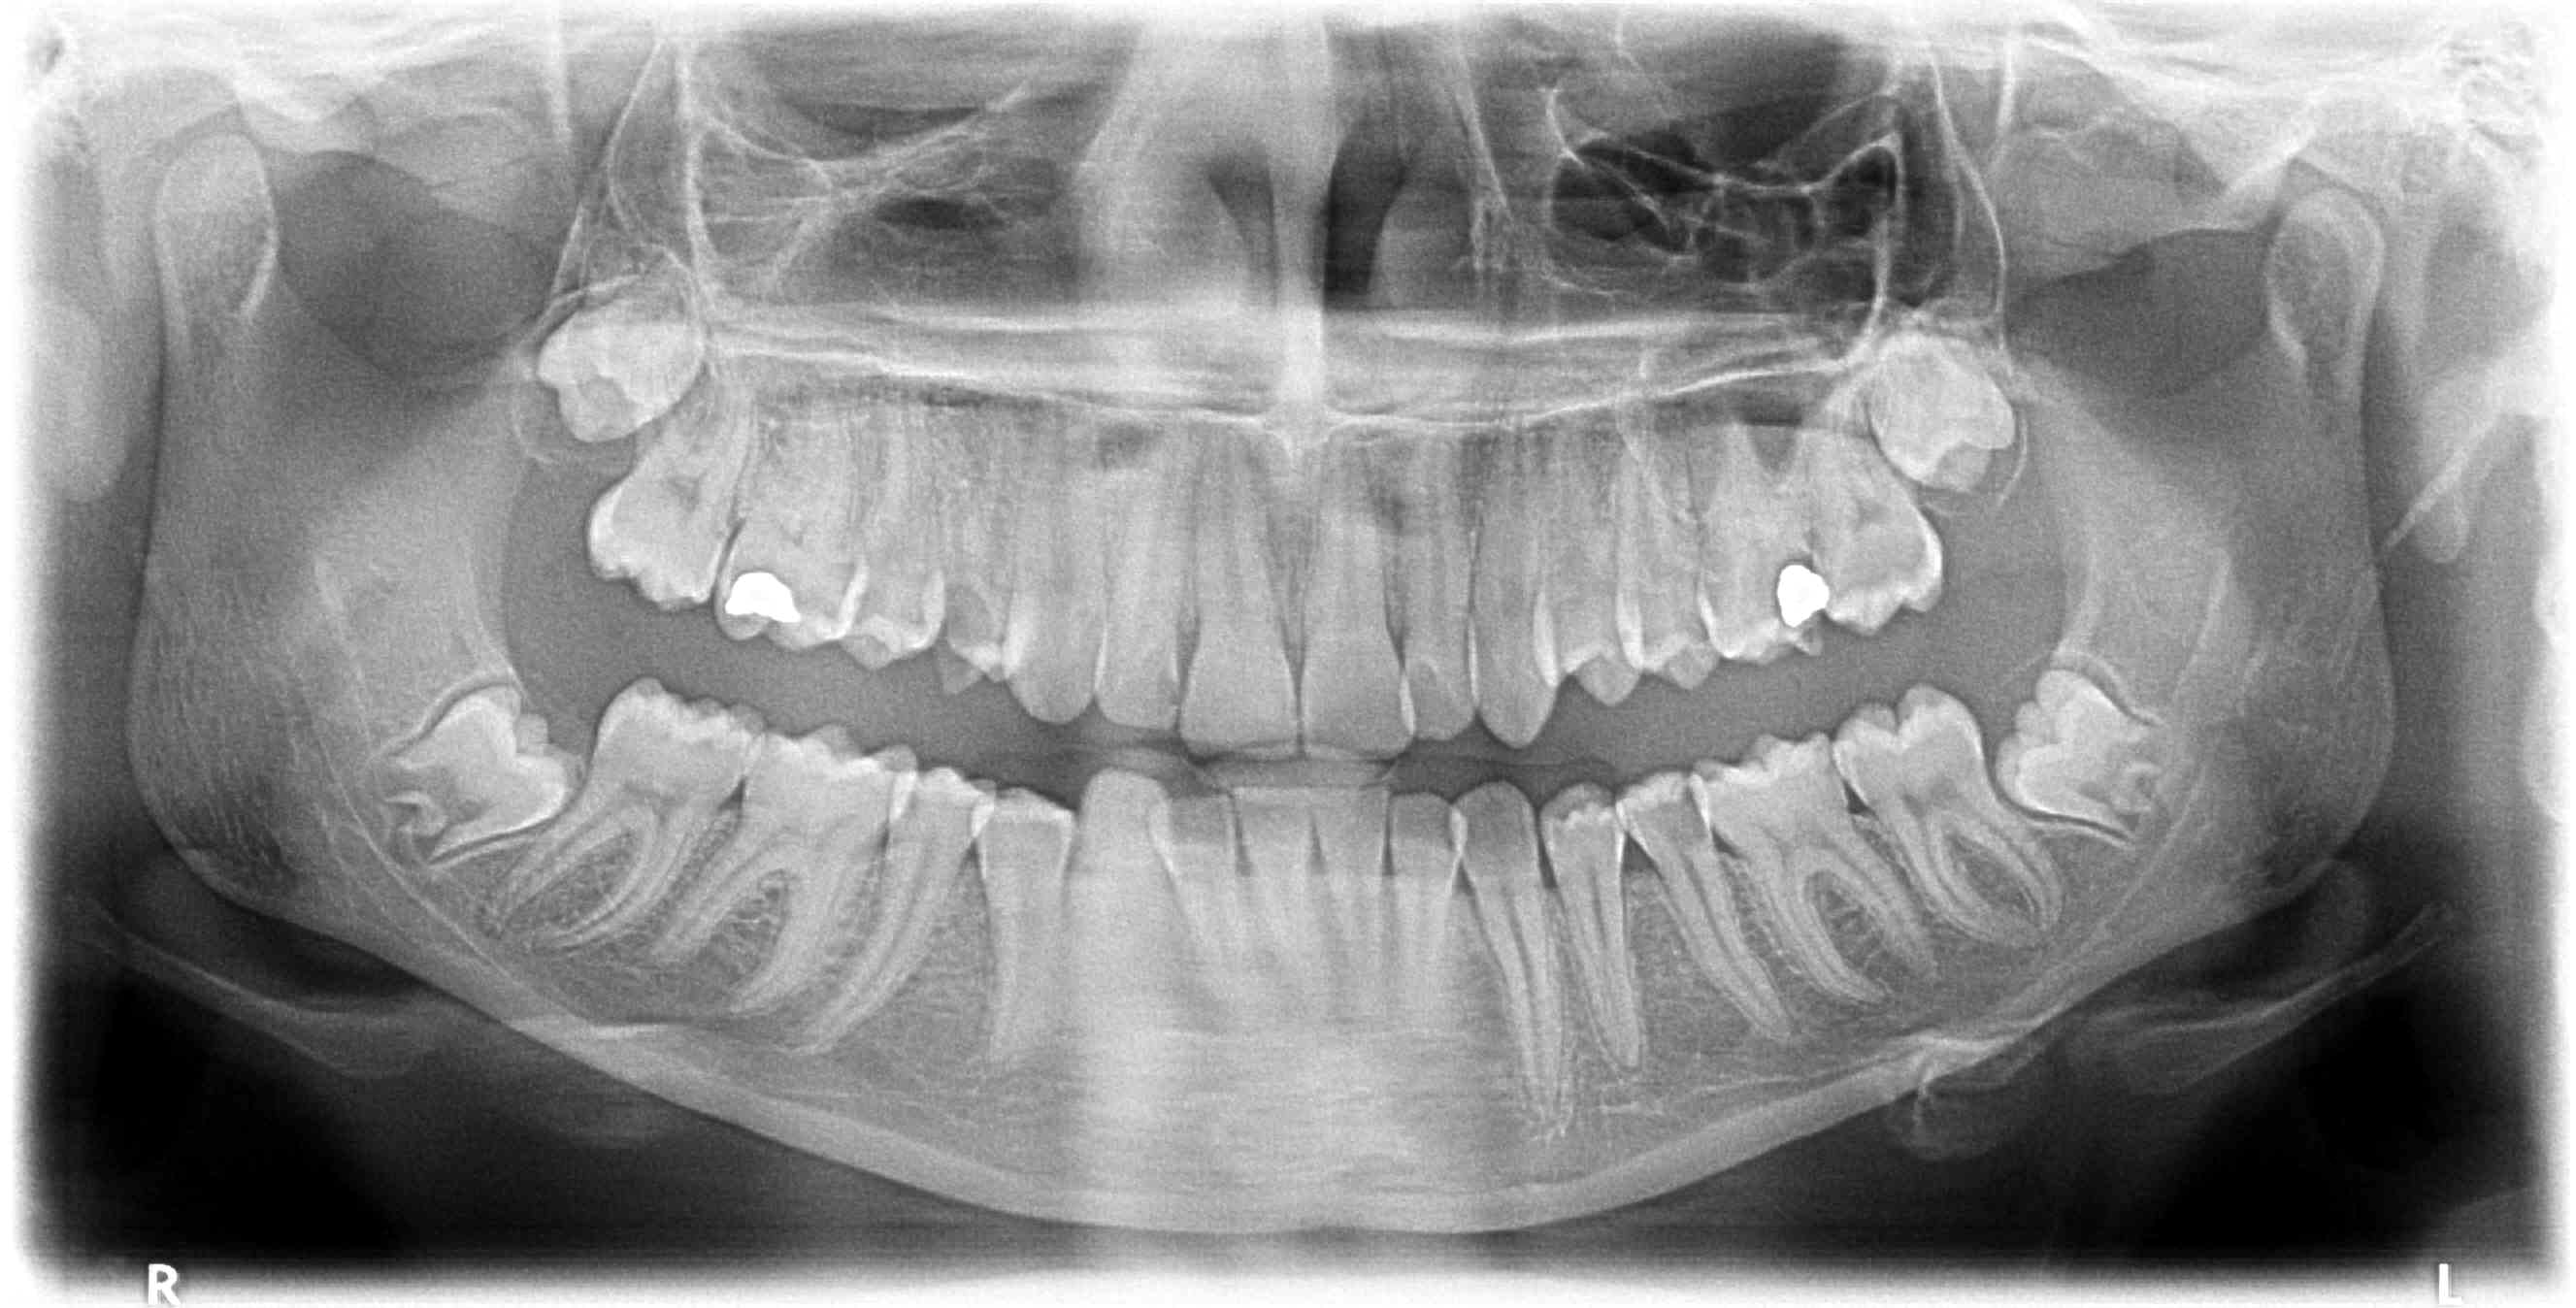

découverte fortuite d'une image étrange sur pano de contrôle secteur sinus gauche. Jeune fille 16 ans.

Inquiétant ou pas ? (ameloblastome ? rare au maxillaire, image étrange)

Déjà soin ou exo de la 6 (là tu as clairement une nécrose avec image apicale toujours tellement floue sur un pano) et ensuite vois si évolution après les soins au secteur 2.

Si vraiment tu doutes fait une imagerie 3D car un ameloblastome maxillaire me paraît peu probable.

Merci, oui oublié de préciser que la 26 est à traiter ?! Semble vivante mais ne va pas le rester longtemps.

En première intention, traitement du secteur 2 mais l'image ne plaît pas . Un ameloblastome ici me paraît également peu concevable.

Non pas de symptôme, 26 asymptomatique, test au froid vraiment peu concluant, je vais la traiter (l'amalgame est infiltré), mais même avec une endo au poil, pas sûr que ça change quelque chose au niveau du sinus.

27 semble vitale sans symptomatologie douloureuse.

lésion peri apex ayant soufflée le plancher du sinus;

test vitalité negatif sur 26

une 3d en confirmation.